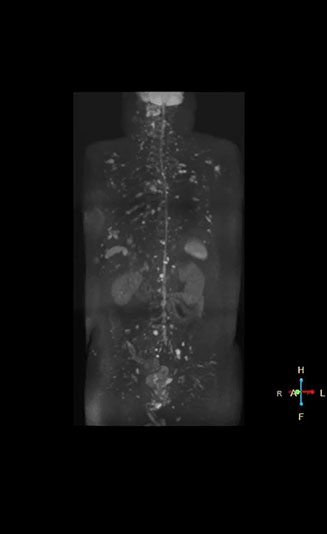

High contrast between lesions and background is beneficial in oncology patients

Radiologist Hiroshi Nobusawa, MD, PhD, explains that the coronal DWIBS protocol for whole body DWI is excellent for visualizing lesions in oncology patients. “About 90% of the DWIBS exams are done in this type of patients. The remainder of DWIBS exams are performed to gain information in cases of fevers of unknown origin,” he says.

“The DWIBS sequence’s value in oncology cases is due to the high contrast it creates between lesions and surrounding tissue. Whole body DWI is requested by physicians who need to clarify TNM staging or determine therapeutic strategies, oncologists in need of diagnosis or follow-up scans, surgeons who need to see the presence of distant lesions that are sometimes difficult to detect by CT before surgery, and urologists for the evaluation of bone lesions, and the effect of chemotherapy and radiotherapy.”

Mr. Naka remembers some cases where DWIBS provided remarkable information. “In one example, DWIBS visualized bone lesions that could not be seen on PET or SPECT. In another case we had found a bone lesion when a normal L-spine scan for narrowing of the disk space was done. One extra DWIBS scan (2 stations, 8 minutes) demonstrated a lesion that later was confirmed to be the primary region of cancer.”

In certain cases, radiologists now choose DWIBS to make diagnoses that used to depend on nuclear medicine studies. “We don’t have SPECT or PET in our hospital, so for instance for visualizing metastasis and monitoring the effect of treatments such as chemotherapy or radiotherapy, we used to refer patients outside the hospital. Now, these patients are sent to MRI for our whole body protocol with DWIBS,” Mr. Naka says.